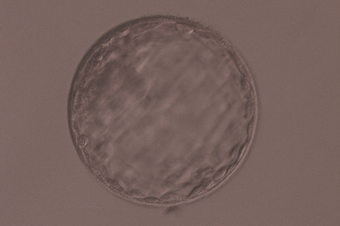

• 顕微授精の様子